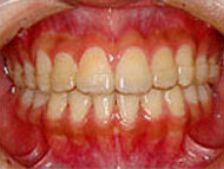

審美ブラケット

メリット

* 目立ちにくい

* 歯みがきしやすい

*ホワイトワイヤーとの組み合わせで更に目立ちにくくなりました。

デメリット

* 装置についた汚れがわかりにくい

* 若干コストが高くなります

※基本的に、金属・セラミックどちらのタイプで治療を行っても期間や効果は変わりません。